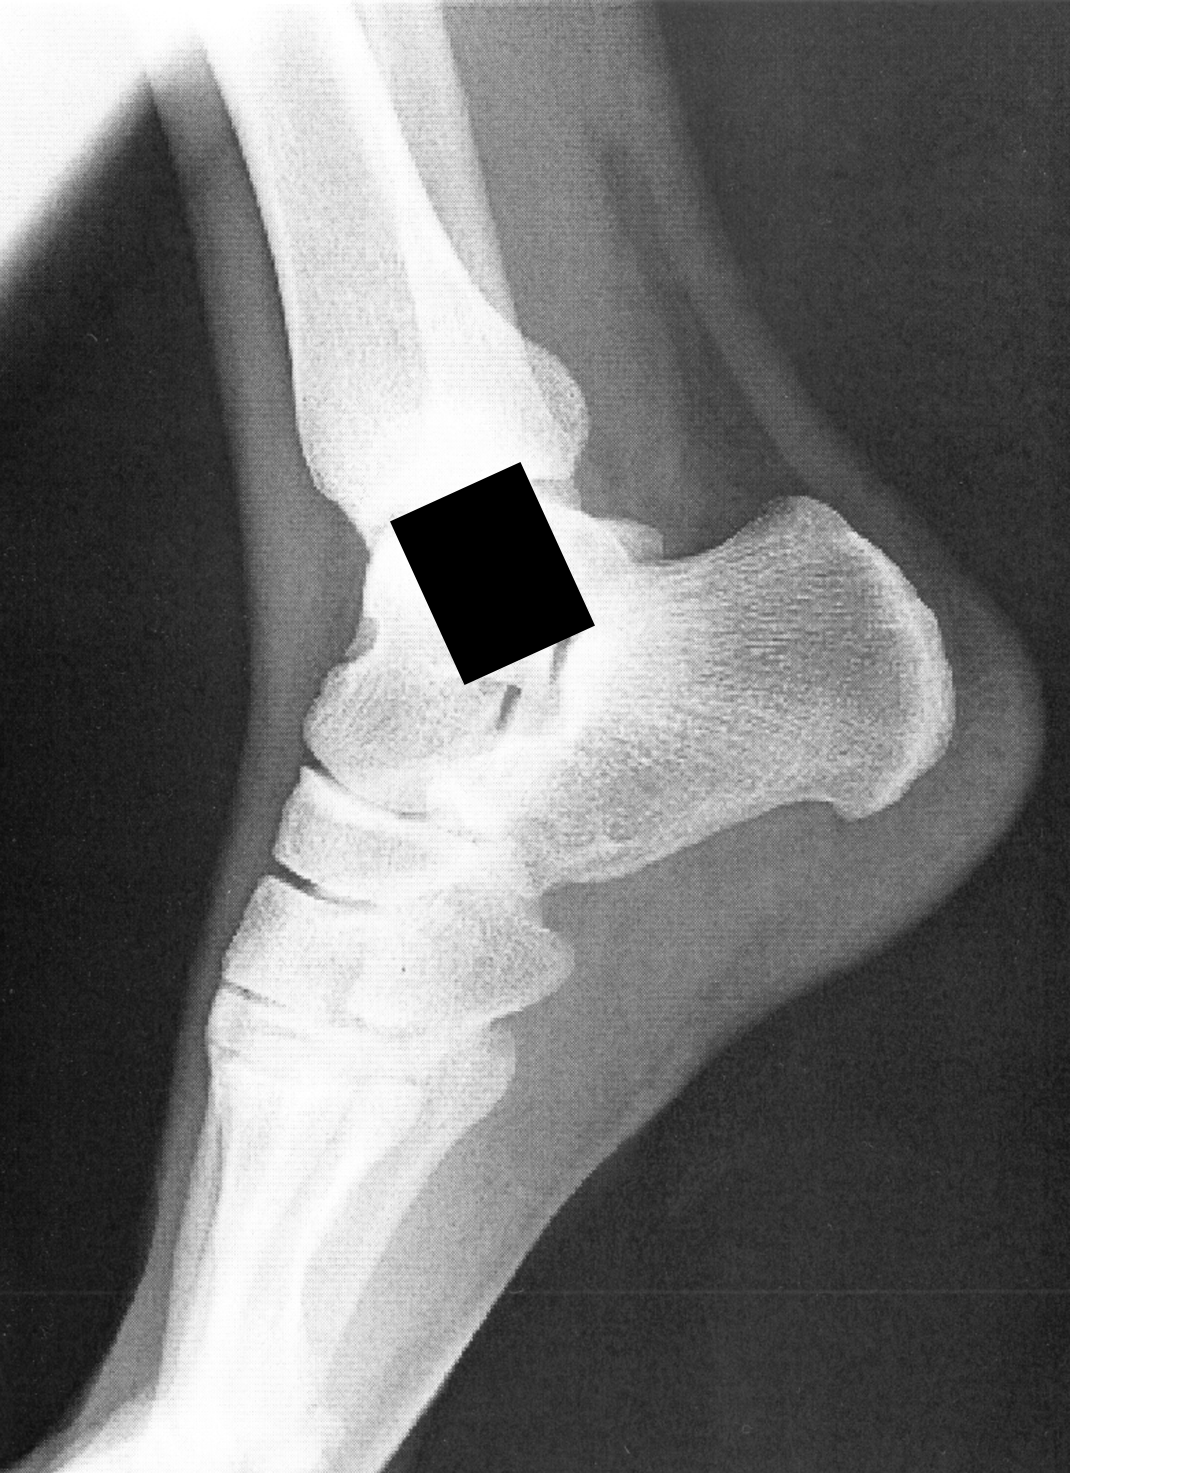

SCP-CN-3743-A的CT图像,摄于SCP-CN-3743-1的右脚脚踝内侧。

认知危害已编辑。

SCP-CN-3743-1指代Site-CN-82高级研究员于渔。2024年11月13日,SCP-CN-3743-1在Site-CN-82的外围过道上休息时由于长时间的穿堂风刺激而突发颜面神经麻痹,并伴随右脚脚踝内侧骨神经的剧烈痛感。随后对其的检查中发现了SCP-CN-3743的存在,其脚踝处的痛感被证明是由SCP-CN-3743-A表情的变化所致。